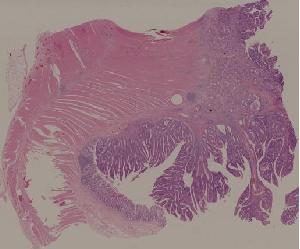

29.结肠腺癌